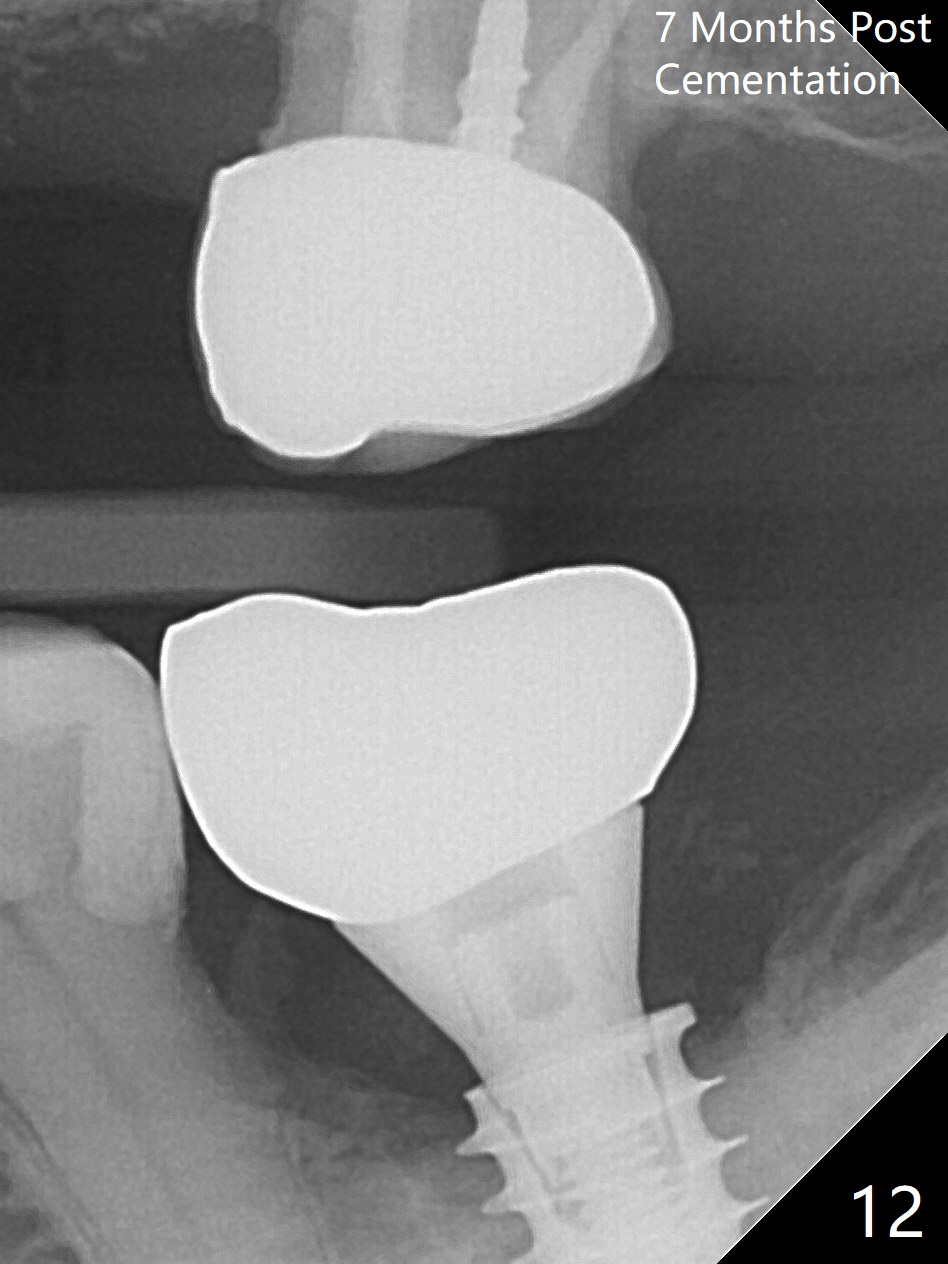

There is no apparent bone loss 4 months postop (Fig.10).  There is chewing pain in spite of occlusal adjustment 7 months post cementation (Fig.11-13: increased radiolucency around the implant).  The crown/abutment is removed and a healing abutment is placed (6x3 mm); the implant is stable.  The patient return for re-evaluation in 3 months (15 months postop); radiolucency appears to reduce (Fig.14).  But there is pain when the healing abutment is being removed.  After local anesthesia, the implant is removed with a wrench.  Following debridement of the osteototomy (intact, although tender), a 5x10 mm dummy implant with SLA surface is placed (Fig.15).  After 5.5 mm tap, a 5.5x8.5 mm implant is placed with >50 Ncm (Fig.16).  A 6.8x5 mm healing abutment is placed, followed by periodontal dressing.  Re-analysis of preop CBCT shows that the bone density at the site is low: 70 units average.  Progressive loading is necessary for this case 4-6 months postop.  The soft and hard tissues around the implant seem to heal 4 months postop (Fig.17).